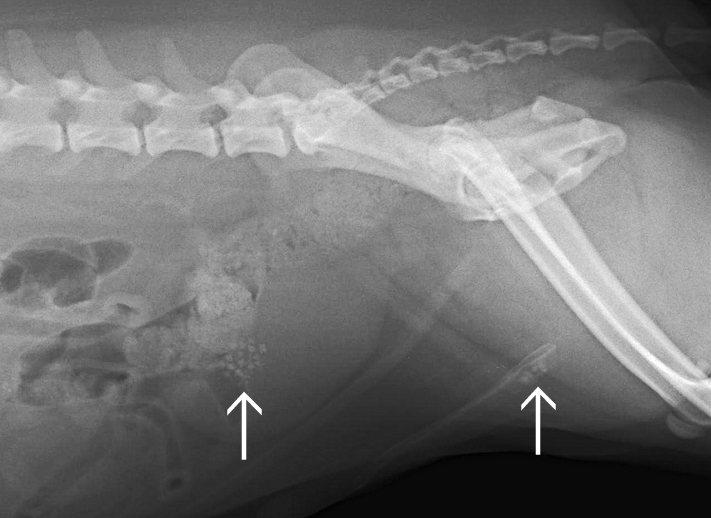

結石により膀胱炎を起こした症例

↑左

膀胱内に多数の結石が存在している

↑右

尿道に結石が詰まってしまっている